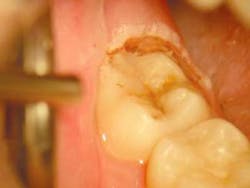

In this case, due to an apprehensive patient, a few drops of 4% Citanest, with the aid of the Wand®, were delivered into the operculum. The tissue was removed with the 980nm diode laser, using the High Fluence Technique developed by the author (Fig. 2). The technique uses higher powers in a gated pulsed mode with water for cooling to accomplish ablation of the tissue at a rapid pace. An excessive time of exposure is often more damaging than the total power delivered, as excessive time allows for conduction of residual energy into the adjacent tissues causing collateral damage and thus postoperative pain. Fifteen watts of power was used gated .05 seconds on and .05 seconds off a 400um fiber and 15 seconds of laser time with water for cooling provided char-free, bloodless ablation. The author believes that this technique is not contrary to the Academy of Laser Dentistry's credo of "using the lowest power to get the job done," but rather it is consistent with it with one addition, "completing treatment in the shortest time while remaining in control." Excessive time can be our enemy when cutting tissue. The author also cautions that the higher fluences and water-cooling he advocates are only to be used with the 980nm wavelength and after proper training in the technique (Fig. 2).